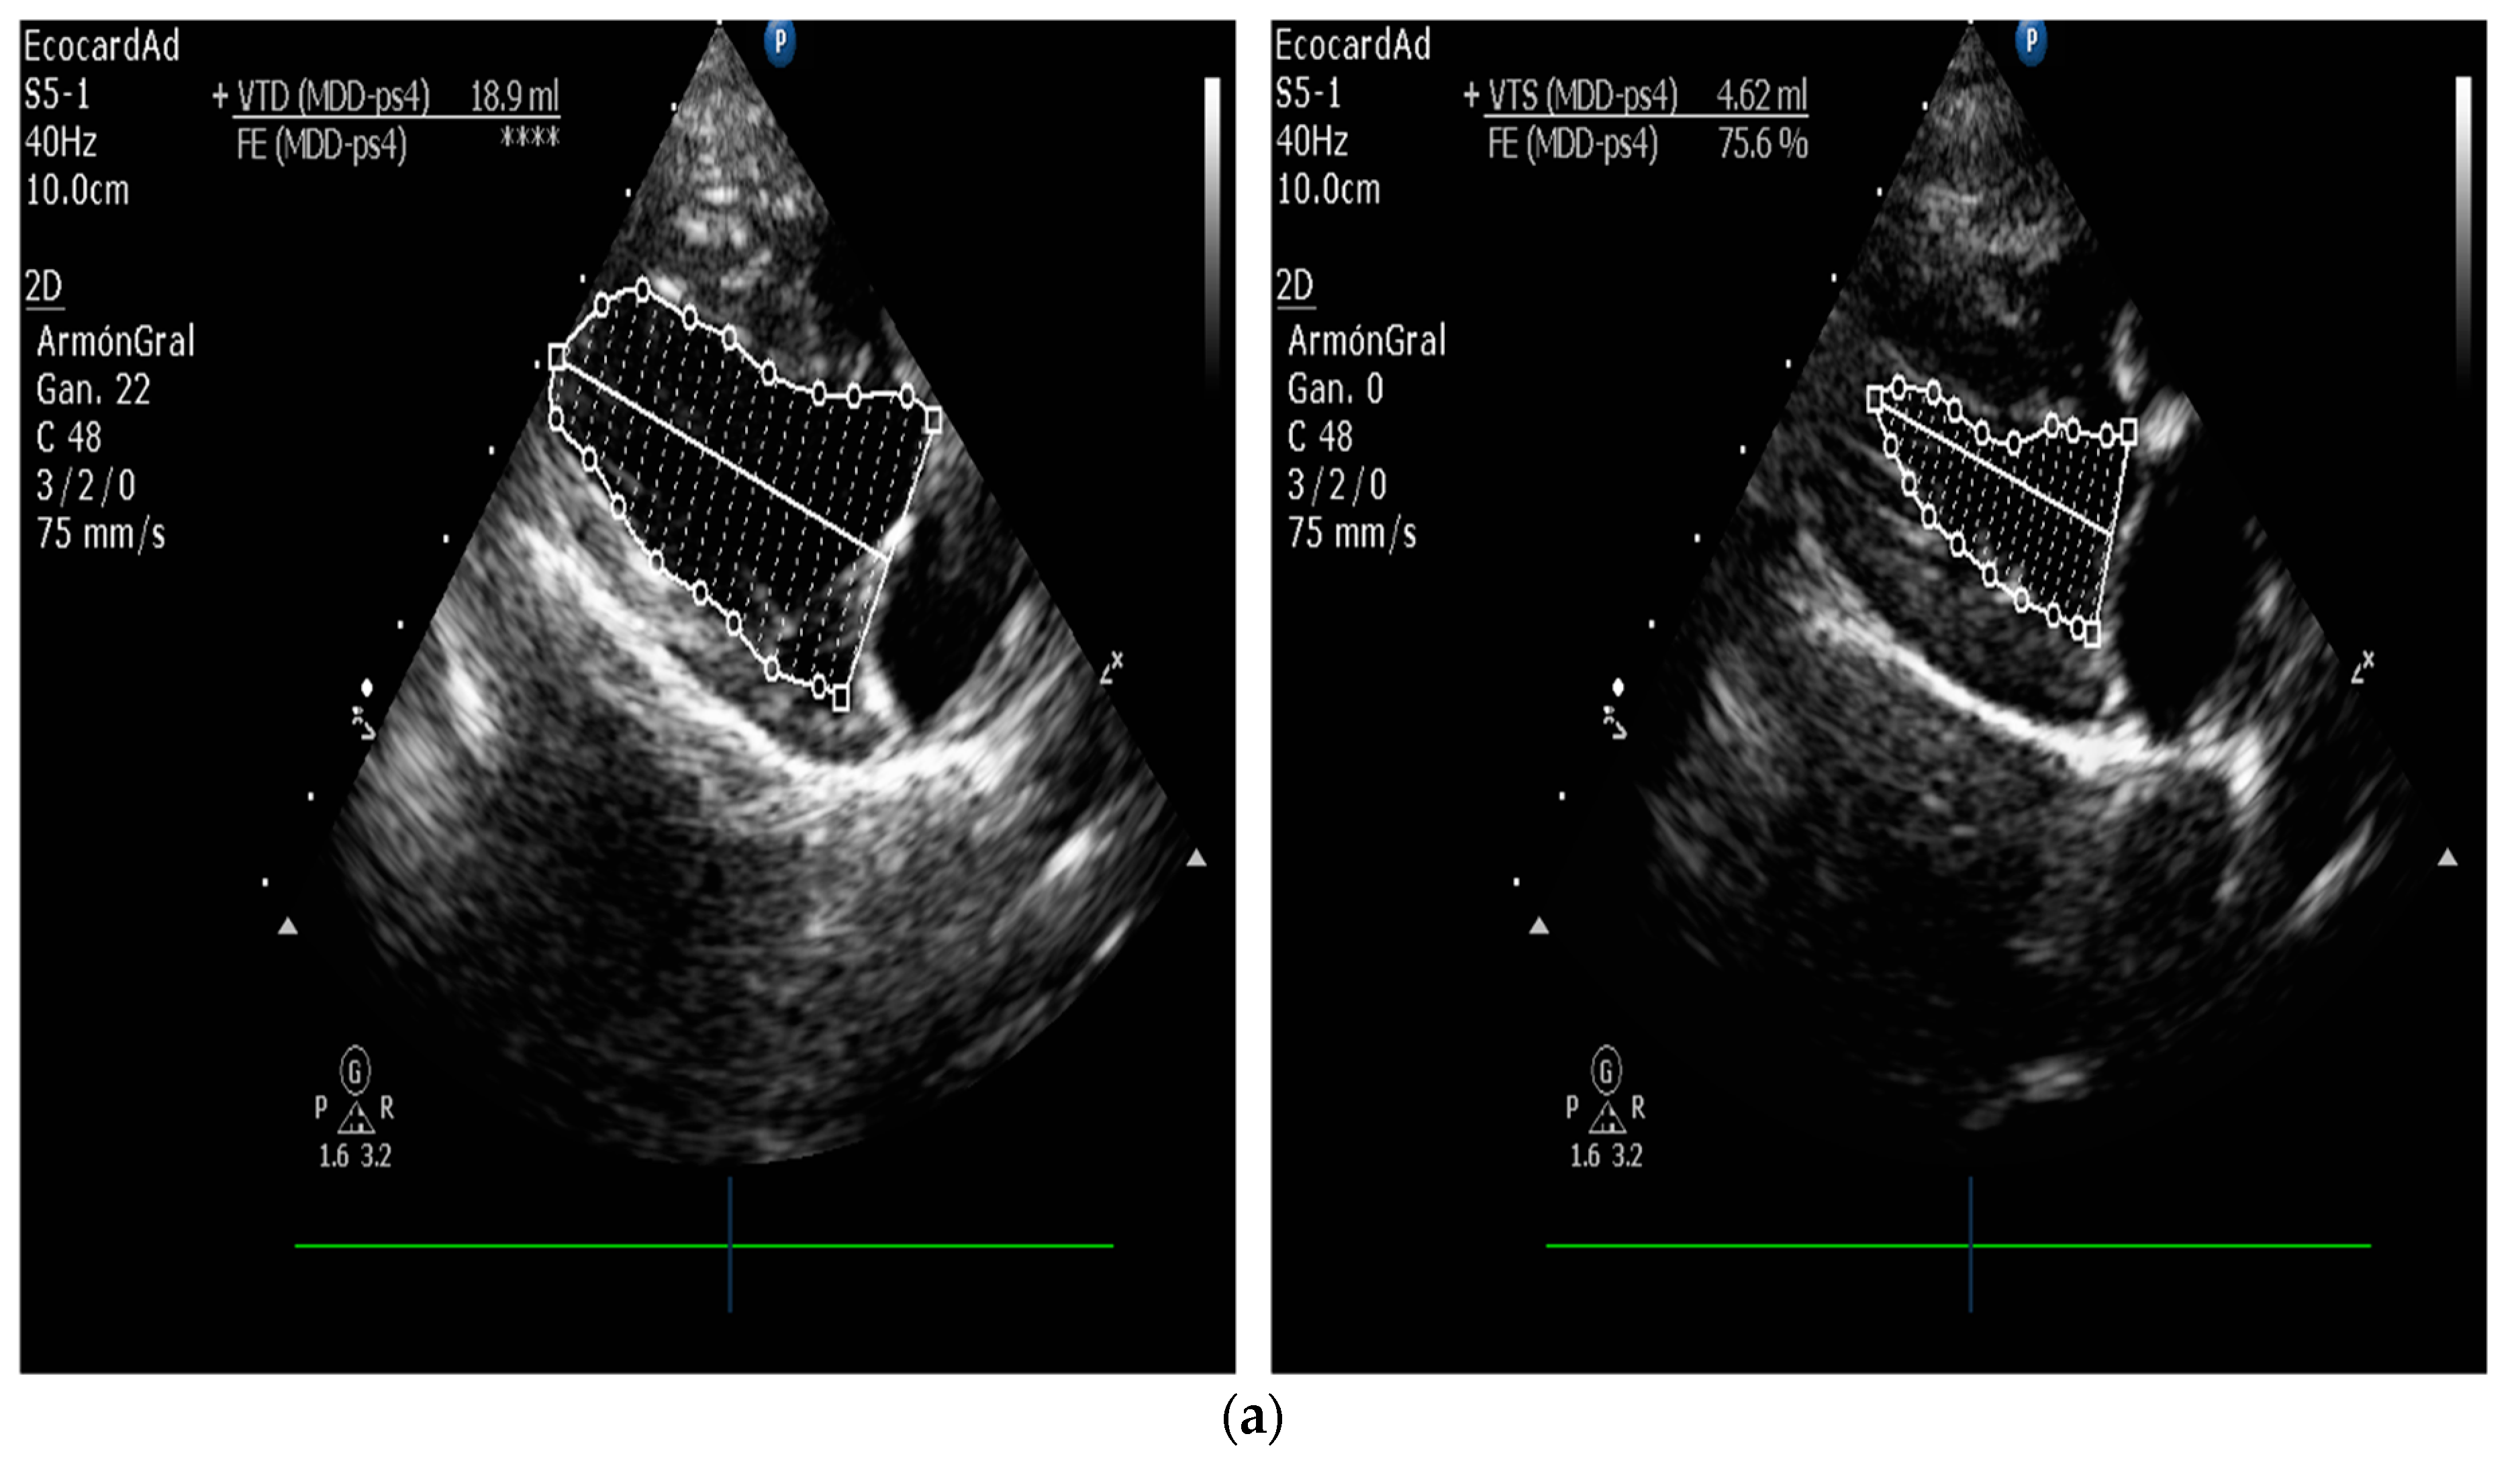

5.1.1. Measurement of Left Ventricular Volume by Simpson’s Method of Disks and Left Ventricular M-Mode

| Measurement of Left Ventricular Volume | M-mode echocardiography is widely used in canine cardiology, but its utility is debated. American Society of Echocardiography recommends against using linear measurements in the human patient. SMOD is recommended [100,102,103]. |